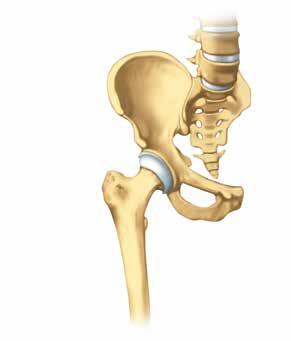

Articolazione artrosica dell’anca

Articolazione sana dell’anca

Nel tempo l’artrosi si sviluppa in modo molto diverso da persona a persona. Può colpire una o più articolazioni. Allo stadio iniziale, poi, è difficile prevedere se ci si deve aspettare dolori, rigidità o limitazioni motorie. A volte gli esami radiologici evidenziano alterazioni marcate, ma la persona colpita se ne accorge appena nella sua vita quotidiana. Viceversa, è possibile che una persona avverta forti dolori senza che la radiografia evidenzi degenerazioni importanti.

A tutt’oggi non è ancora chiaro quali siano i fattori che influenzano l’entità dei disturbi. È importante sapere, però, che una diagnosi di artrosi non vuol dire automaticamente che bisogna aspettarsi forti limitazioni in futuro.